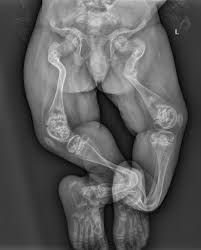

Osteogenesis imperfecta

Osteogenesis imperfecta (OI) is a genetic disorder that prevents the body from building strong bones. People with OI might have bones that break easily, which is why the condition is commonly called brittle bone disease.